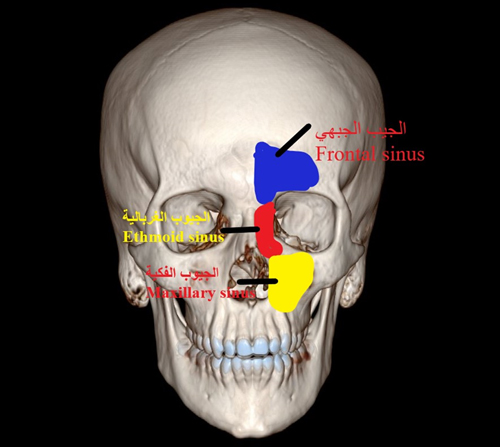

ما هي وظيفة الجيوب الأنفية؟ يساعد على تخفيف وزن الجمجمة ،تحسين نبرة الصوت ، إنتاج المخاط ، والمساعدة في الحفاظ على رطوبة الهواء الذي نتنفسه من خلال الأنف .

بشكل عام من استطبابات هذا النوع من العمليات يكون في حال تعرض المريض إلى التهابات متكررة في الجيوب الأنفية أو في حالة الحساسية الأنفية مع أو بدون وجود الاورام الحميدة الأنفية التي لم تستجيب للعلاج الدوائي